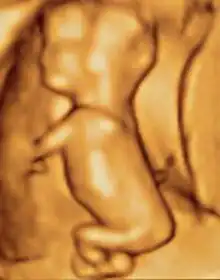

A dating scan at 12 weeks

Obstetric ultrasonography is routinely used for dating the gestational age of a pregnancy from the size of the fetus, determine the number of fetuses and placentae, evaluate for an ectopic pregnancy and first trimester bleeding, the most accurate dating being in first trimester before the growth of the foetus has been significantly influenced by other factors.[22] Ultrasound is also used for detecting congenital anomalies (or other foetal anomalies) and determining the biophysical profiles (BPP), which are generally easier to detect in the second trimester when the foetal structures are larger and more developed.[23]

The safety of frequent ultrasound scanning has not been confirmed. Despite this, increasing numbers of women are choosing to have additional scans for no medical purpose, such as gender scans, 3D and 4D scans.[27] A normal gestation would reveal a gestational sac, yolk sac, and fetal pole.[28]